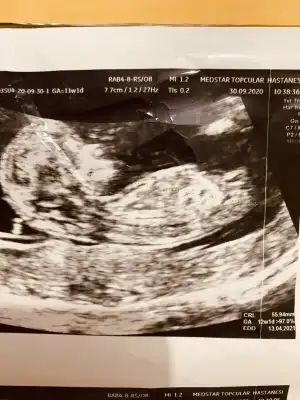

Tamam teşekkür ederim haftaya tekrar atarımİkiside kız görünüyor ama bu haftalar yanitir siz 11 12 13 haftalar paylasin

Nubu çok karışık net varsa paylasinCanım biz eşimle baya inceledik. Bizimkisi baya örnek kız bebek nubu vermiş ultrasonda. Ama sen daha tecrübelisin sen ne diyorsun nubuna![]()